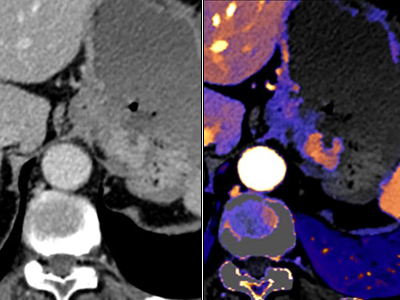

Le pouvoir de la tomodensitométrie à détection spectrale au profit de la confiance diagnostique, toutes spécialités confondues.